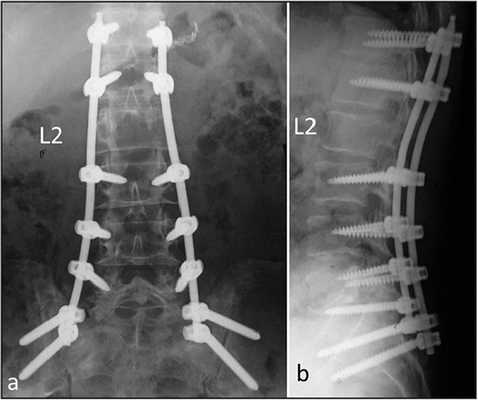

Проведен анализ оперативного лечения 48 пациентов (16 мальчиков и 32 девочки) в возрасте от 1 года 2 мес. до 7 лет с врождённой деформацией на фоне боковых и заднебоковых и задних полупозвонков в поясничном отделе и зоне грудопоясничного перехода (таблица).

Боковые полупозвонки создавали сколиотическую деформацию, заднебоковые - формировали кифосколиотическую. Угол сколиотической деформации составлял от 200 до 450, кифотического искривления - от 120 до 560.

Методика хирургического вмешательства заключалась в одномоментной трехэтапной операции из комбинированных доступов (переднебокового и дорсального):

1. Положение пациента на боку противоположной стороне локализации аномального позвонка. Осуществляли переднебоковой доступ к вершине деформации. При расположении аномального позвонка в зоне грудопоясничного перехода выполняли торакофренолюмботомию с отсечением ножки диафрагмы. При локализации полупозвонка в поясничном отделе позвоночника выполняли внебрюшинный люмботомический доступ. Перевязывали и пересекали сегментарные сосуды. Дугообразно рассекали и отслаивали переднюю продольную связку над аномальным телом позвонка и соседними к нему межпозвонковыми дисками (патент № 2355336 от 20.05.2009 г.). Выполняли экстирпацию тела бокового или заднебокового полупозвонка с прилегающими к нему дисками. В результате формировался клиновидный дефект с основанием, обращенным к вершине деформации, и осуществляли освобождение позвоночного канала. При экстирпации тела аномального позвонка из переднебокового доступа старались максимально удалить до его основания.

2. Больного поворачивали на живот, не зашивая первой послеоперационной раны. Выполняли разрез вдоль линии остистых отростков тел позвонков, центр которого проходил через вершину деформации. У пациентов раннего возраста скелетировали дуги тел позвонков только со стороны врожденного порока. У детей старше 4 лет скелетирование задних опорных элементов осуществляли симметрично с двух сторон. Удаляли полудугу полупозвонка и остатки ее основания. После удаления полудуги полупозвонка и ее основания из дорсального доступа дополнительно на стороне противоположной удаленному полупозвонку осуществляли частичную резекцию нижней части дуги вышележащего позвонка и верхней части дуги нижележащего позвонка от линии остистых отростков латерально до края дуги. Частичную резекцию выполняли на 1/3 своей ширины нижней части вышележащей нормальной дуги и частичную клиновидную резекцию 1/3 своей ширины верхней части нижележащей нормальной дуги. В результате формировался дефект треугольной формы с основанием, обращенным к остистым отросткам. Выполненная частичная клиновидная резекция задней опорной колонны позвоночника на стороне противоположной аномальному позвонку позволяла создать дополнительную мобильность позвоночно-двигательного сегмента при коррекции деформации. Кроме этого, на стороне удаленного полупозвонка осуществляли продольную остеотомию соседней к нему нормальной дуги (или двух соседних дуг) позвонка, которая была отклонена от правильной вертикальной оси позвоночника с уровня аномального позвонка. Остеотомию выполняли строго вдоль линии остистого отростка на протяжении 2/3 высоты дуги нормального позвонка. Осуществляли остеотомию вдоль линии остистого отростка вышележащей дуги на протяжении 2/3 своей высоты, при отклонении верхней части позвоночника от вертикальной его оси с уровня порочного позвонка.